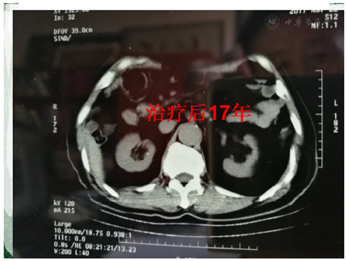

术后放疗、增敏化疗、中药生物制剂新综合治疗,下消化道急性放射反应2级。脾区腹膜转移灶治疗后1个月CT复查肿物大部缓解(PR),以后逐年缩小,治疗8年后仍可见14 mm×11 mm残留灶(图3),17年肿瘤完全缓解(CR)(图4),局部纤维化,未影响生活质量(图5),颈部淋巴结转移灶综合治疗后1个月为CR。CEA值接近了自己的正常值2.1ng/ml,3次以上检查的最低值视为该患者正常值,卡氏评分100(图6)。